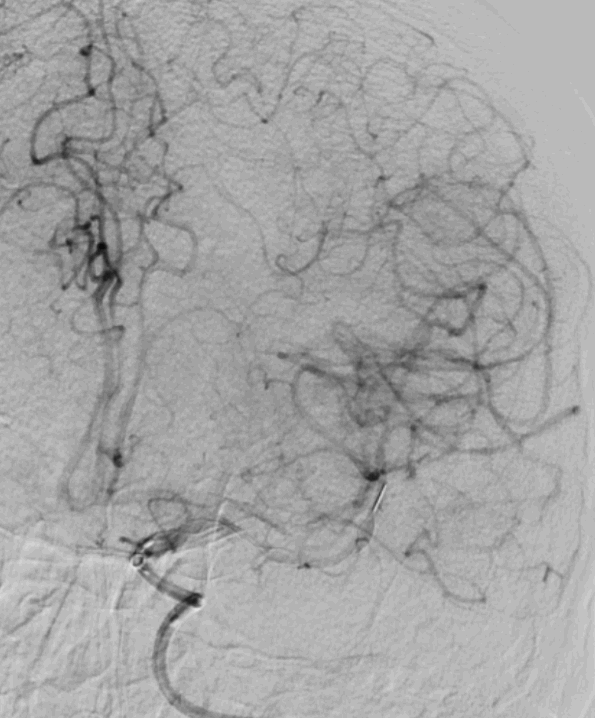

最后路径手推造影,造影确认脑血流完全恢复,mTICI 3级。

术后复查CTA:提示左侧大脑中动脉通畅,支架在位。